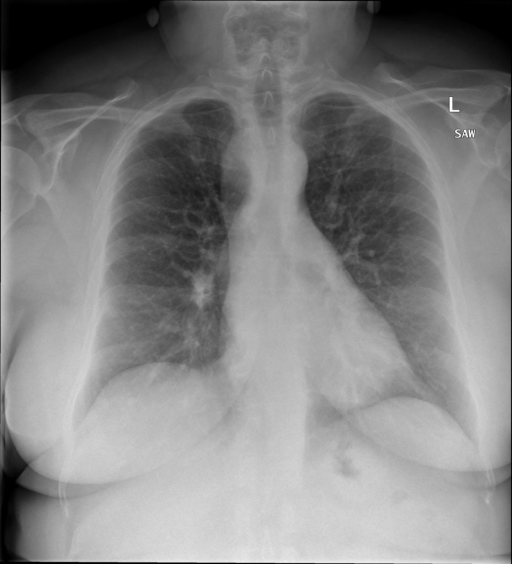

|X光影像|诊疗报告(医生)|

||右侧主动脉突出观察到。心脏大小正常。胸部未发现明显的肺气肿、胸膜积液或可疑的肺部病变。报告指出已知右侧主动脉情况正常。|

```bash

>> X光影像路径:./data/Xray/861_1.png

>> 用户:这是一张什么图?

>> XrayGLM:这张图片显示的是一张肺部检查的X光片。

>> 用户:请描述这张胸部X光片的诊断结果

>> XrayGLM:心脏大小正常,肺部清晰。没有急性心肺疾病的证据。

>> 用户:是否存在肺气肿?

>> XrayGLM:没有肺气肿。心脏大小正常,肺部清晰。没有发现急性心肺疾病的证据。

>> 用户:平时饮食该注意什么?

>> XrayGLM:饮食应该健康,均衡。建议增加蛋白质的摄入量,因为蛋白质有助于维持肌肉和骨骼的健康。多食用蔬菜、水果、全谷物以及健康的脂肪来源如橄榄油、鱼类等可以帮助获得足够的维生素和矿物质。此外,避免过度饮酒或吸烟,这些习惯可能会对心脏健康产生负面影响。

```